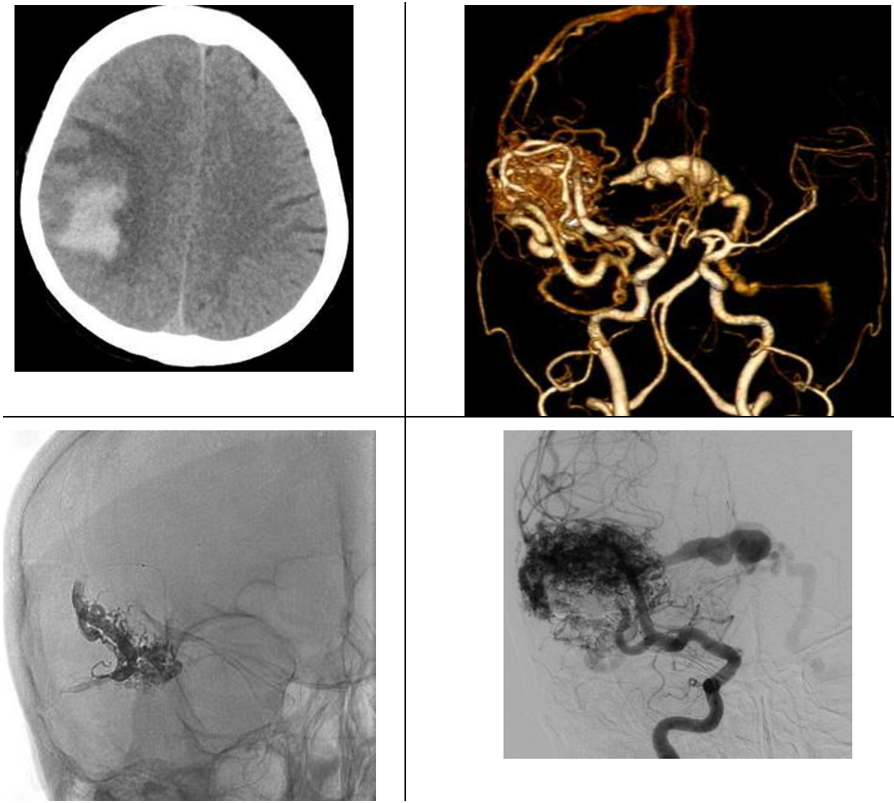

Dị dạng mạch AVM vỡ

Bệnh nhân nữ 67 tuổi có xuất huyết lớn trong nhu mô thái dương-phải do dị dạng AVM vỡ. Dị dạng mạch này được can thiệp nút tắc chọn lọc một phần chảy máu bằng Onyx.